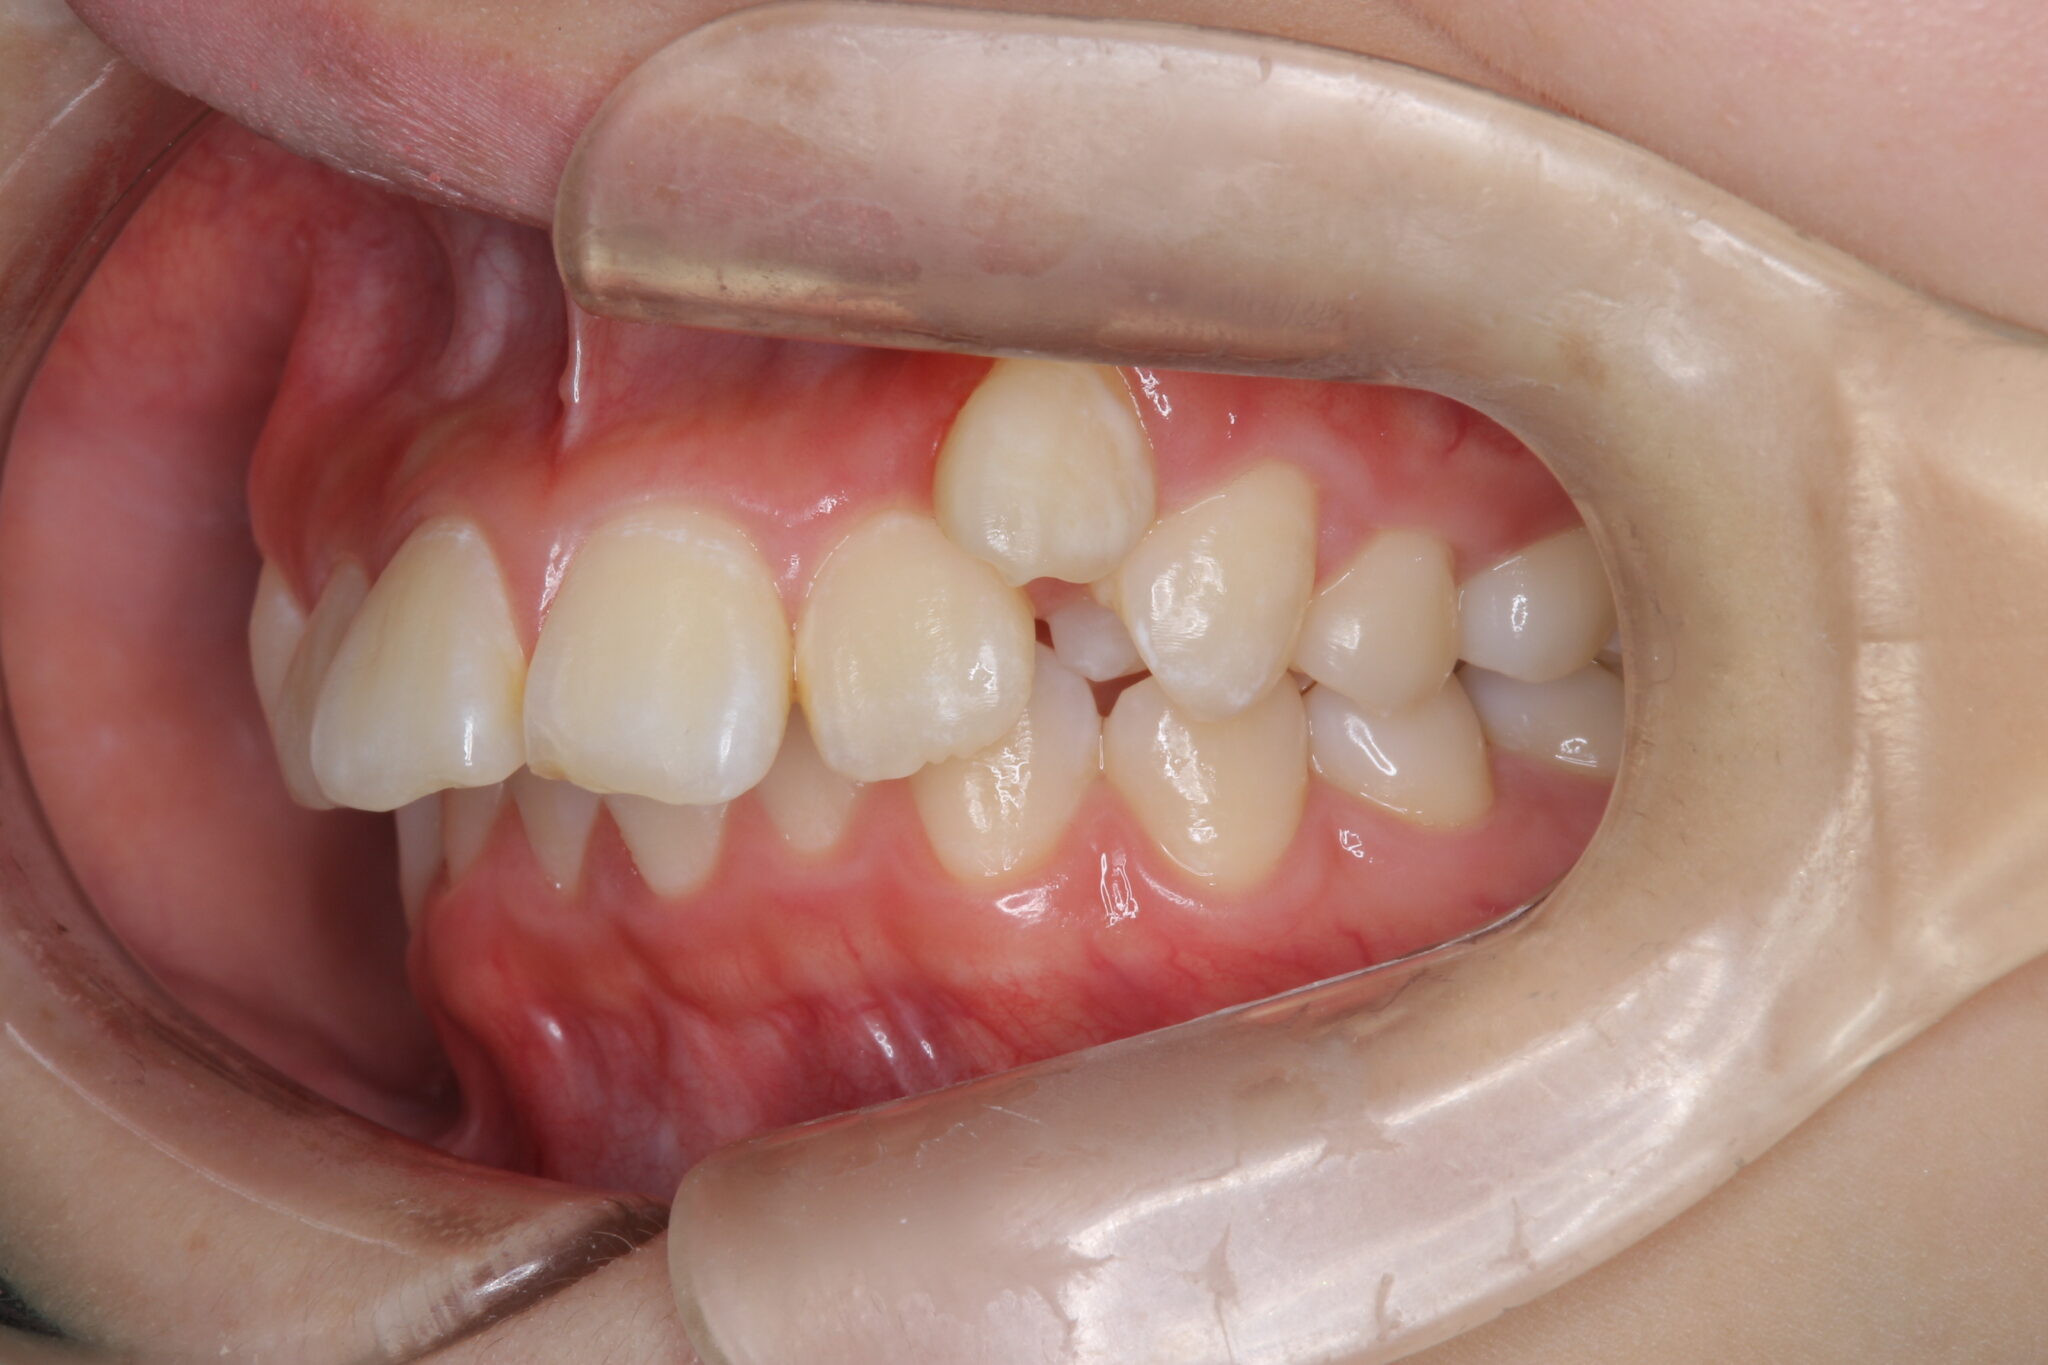

八重歯と出っ歯が気になる

形態的には上顎前突(出っ歯)の骨格

上顎左側の犬歯は低位唇側転位している(八重歯)

下顎前歯は1本欠損した3前歯の状態